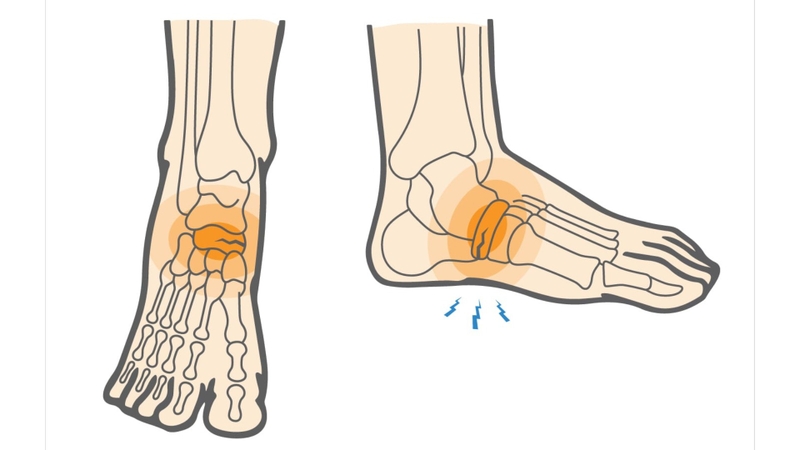

Rạn xương bàn chân có nguy hiểm không? -2

Có nhiều yếu tố có thể dẫn đến nguy cơ rạn xương bàn chân

Dấu hiệu rạn xương bàn chân

Dấu hiệu của rạn xương bàn chân có thể kể đến như:

• Đau đớn cục bộ: Cảm giác đau tại vị trí chấn thương là biểu hiện phổ biến nhất. Đau có thể ở mức độ từ nhẹ đến nặng tùy thuộc vào mức độ và đặc điểm của rạn xương.

• Sưng và đau khi chạm: Khu vực xung quanh vị trí rạn xương thường sưng lên và có thể đau khi chạm vào. Sưng và đau có thể xuất hiện ngay sau chấn thương hoặc sau một thời gian ngắn.

• Đỏ hoặc xanh tái: Da xung quanh vùng chấn thương có thể trở nên đỏ hoặc xanh tái do viêm nhiễm và sưng tăng lên.

• Tê hoặc cảm giác buồn chân: Cảm giác tê hoặc buồn chân có thể xuất hiện do áp lực lên dây thần kinh hoặc viêm nhiễm gây ra.

• Khó di chuyển hoặc không thể đặt trọng lượng lên chân: Nếu chấn thương nghiêm trọng, có thể gây ra khó khăn trong việc di chuyển hoặc ngay cả không thể đặt trọng lượng lên chân.

• Tiếng kêu khi di chuyển: Trong một số trường hợp, có thể nghe thấy tiếng kêu hoặc cảm giác rung lên khi di chuyển xương bị rạn do các mảnh xương chạm vào nhau.

Những dấu hiện này thường cho thấy có vấn đề về xương bàn chân và cần được đánh giá và điều trị bởi một chuyên gia y tế.

Rạn xương bàn chân có nguy hiểm không? -4

Rạn xương bàn chân thường gây đau đớn cục bộ